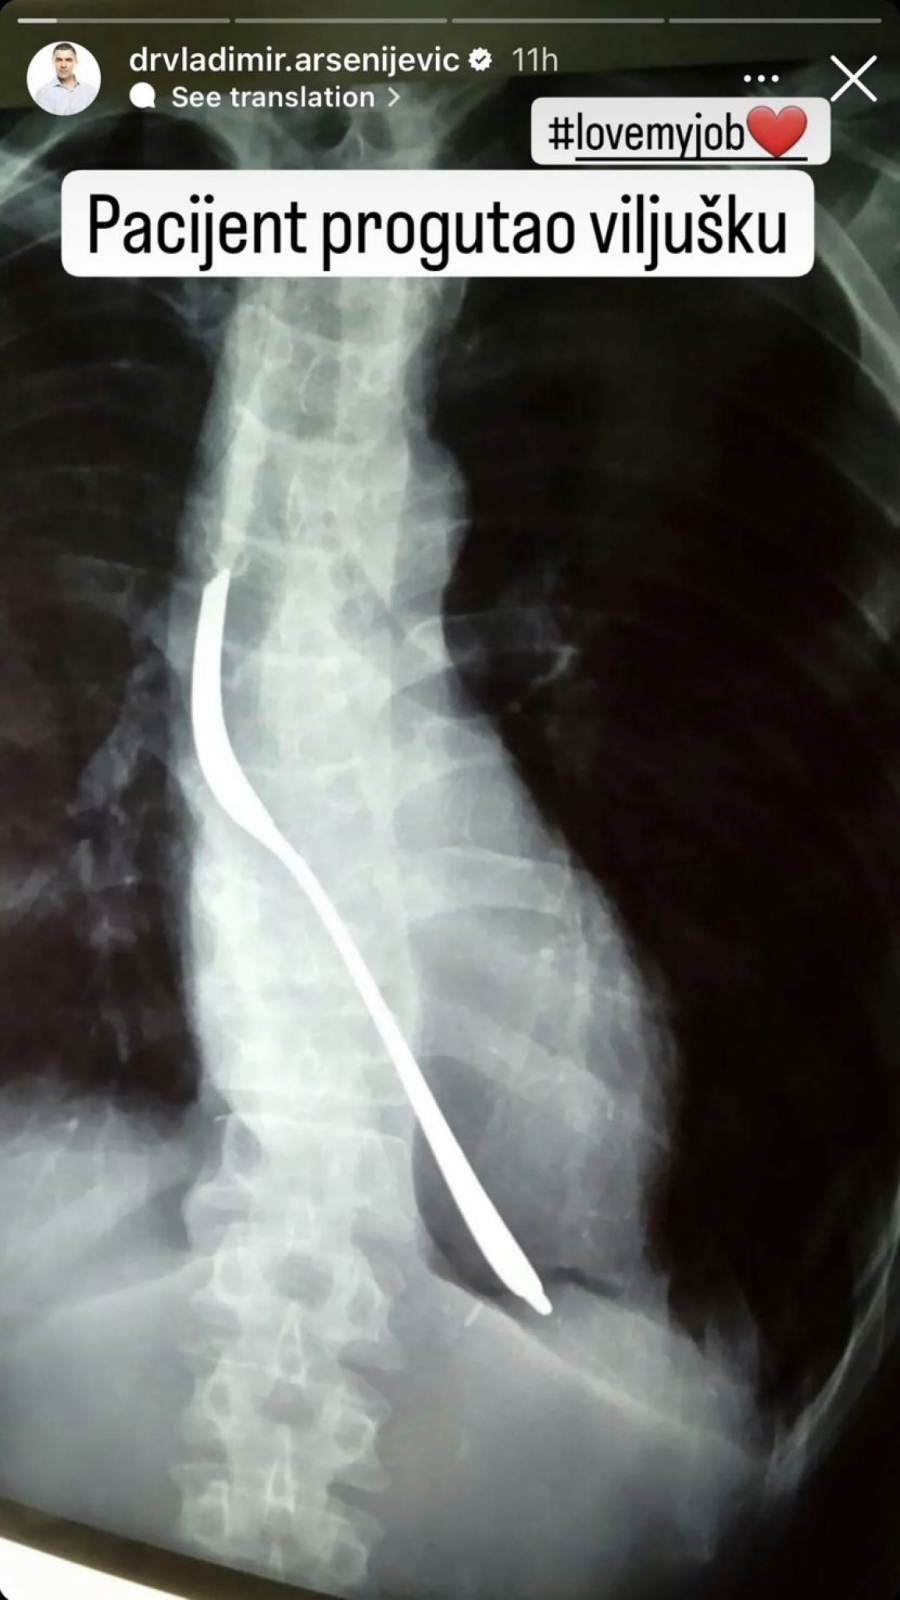

Naime, dr Vladimir Arsenijević, načelnik prijema u Urgentnom centru KC Srbije objavio je na svom Instagram nalogu rendgenski snimak pacijenta koji je progutao ni manje, ni više nego viljušku.

"Pacijent progutao viljušku. Ja volim moj posao", napisao je Arsenijević.

Pojedinosti o pacijentu nisu poznate i pretpostavlja se da će strano telo biti uklonjeno operativnim putem.